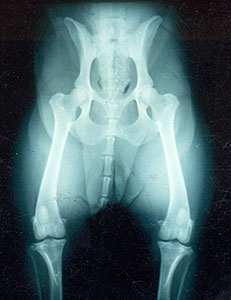

At 8 months of age, this guy already has very bad hips... The malformation is so obvious that most people can see the severe bilateral (both sides) dysplasia. The acetabulum (cup in which the head of the femur moves) is almost non-existent, and the head of the femur (the round 'ball' at the top of the femur - the thigh bone) is flattened and not deeply seated into the acetabulum. This puppy could barely walk, he was in a lot of pain, and his condition only worsened as he aged. You increase the probability of having puppies with good joints if the parents have good joints.